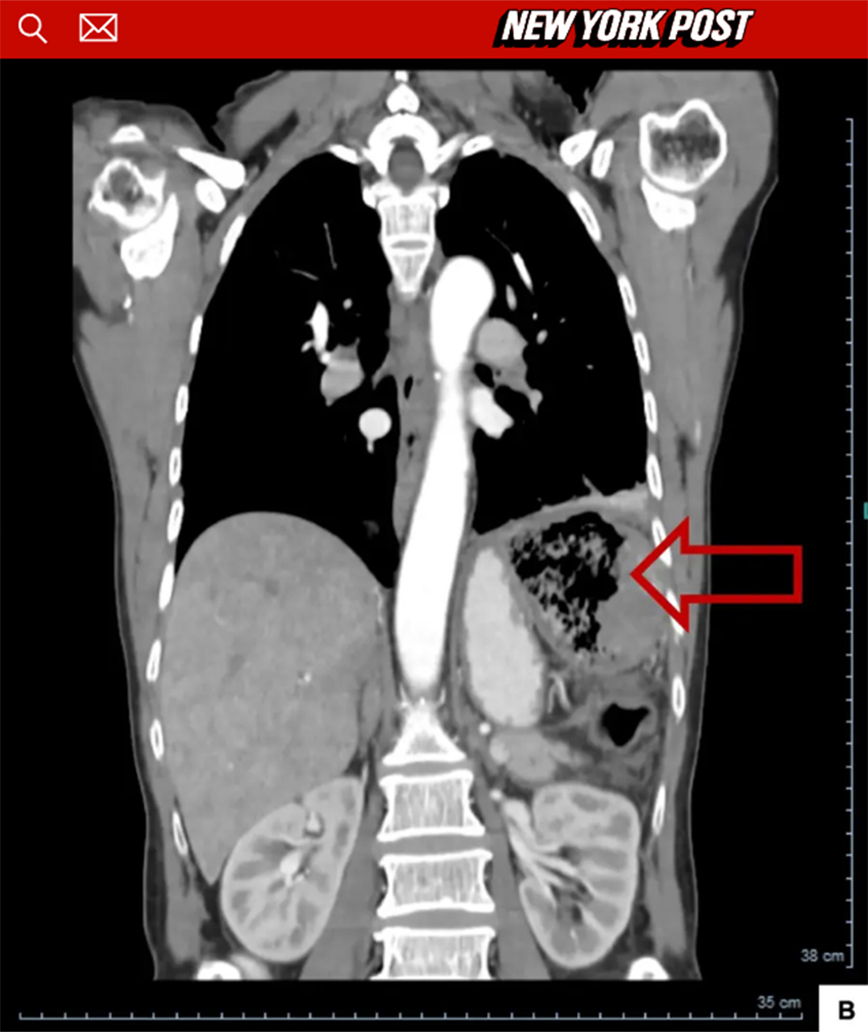

Μάλιστα, μπορεί να υποβλήθηκε σε εξετάσεις και ακτινογραφίες τα επόμενα χρόνια, όμως οι γιατροί ποτέ δεν μπήκαν στον κόπο να δουν καλύτερα, τι ήταν το περίεργο πράγμα που εντόπιζαν στο στομάχι.

Τότε, πήγε στο νοσοκομείο και μετά τις απαραίτητες εξετάσεις αυτή την φορά οι γιατροί κατάλαβαν ότι κάτι δεν πήγαινε καλά, μέχρι που εντόπισαν ότι πρόκειται για μια ξεχασμένη γάζα από το προηγούμενο χειρουργείο.